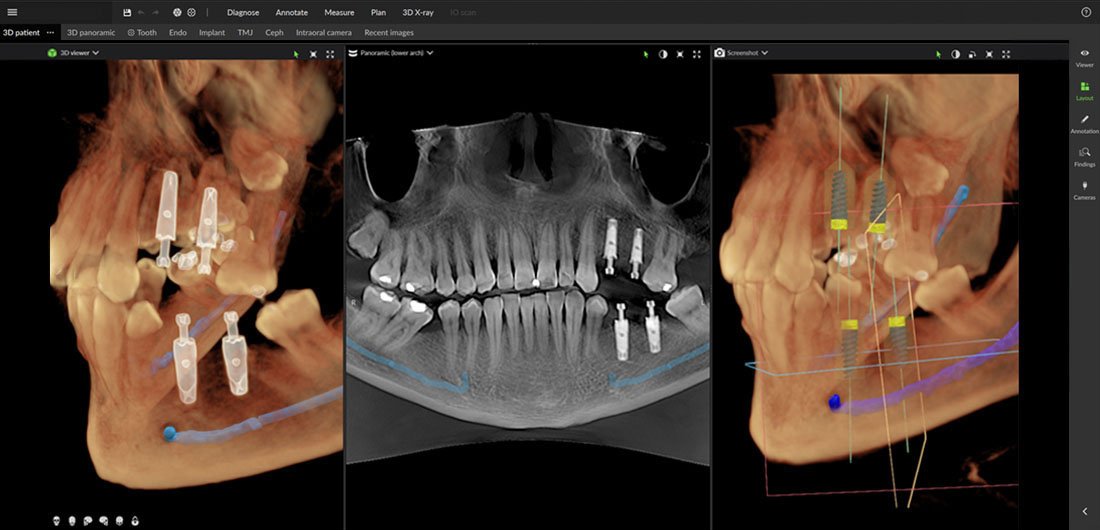

Implant placement

Whether it’s a single implant placement or the application of the All-on-4 technology, the DEXIS OP 3D LX enables multidimensional imaging for pre-surgical diagnosis and supports the most precise implant placement.

This 3D technology-based multimodal imaging platform covers the full spectrum of dental imaging needs, from endodontics to the most complex implant cases.

The system supports perfect visualization by enabling the specialist to integrate 3D data with intraoral scan information, providing a complete view of the patient’s anatomy.